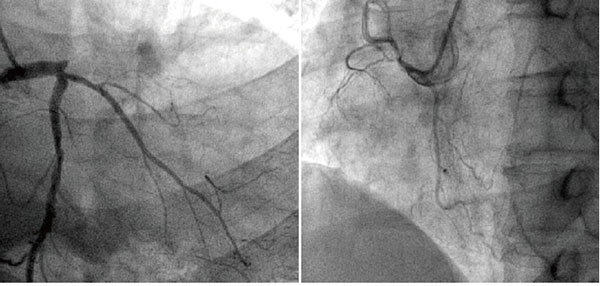

冠脈造影

冠狀動脈是給心臟供血的血管,當這個血管或者它的分支出現病變,我們就會患上冠心病(心肌缺血)。在輕度病變的時候, 患者沒有癥狀,或者出現心絞痛。嚴重病變的時候會有形成心肌梗死的風險。

前臨床常用的冠狀動脈造影檢查包括冠狀動脈CT血管造影(CTA)和介入冠狀動脈造影兩種,都是評價動脈是否存在病變以及指導治療的重要手段,兩者各有優缺點,也各有利弊,在不同情況下選擇不同的檢查方式,需要根據情況來決定,不能一成不變的認為CTA好或者介入造影更好。